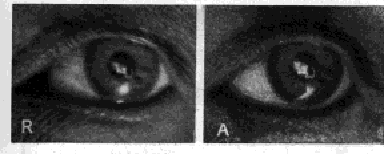

Fig. 26. Image of Electric Filament on the Front of the Lens

R, rest; A, accommodation. Under the magnifying glass no change can be observed in the size of the two images. The image at the right looks larger only because it is more distinct. To support the theory of Helmholtz it ought to be the smaller. The comet's tail at the left of the two images is an accidental reflection from the cornea. The spot of light beneath is a reflection from the light used to illuminate the eye while the photographs were being taken. It took two years to get these pictures.